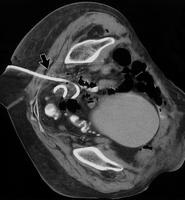

穿过坐骨大孔的结构有梨状肌,坐骨神经,股上和股下血管,股上神经,到大腿的股后皮神经,到闭孔内肌的神经,以及阴部内血管。坐骨神经由骶丛神经向下延伸而形成,从坐骨大孔前三分之一穿出,在骶嵴韧带髂嵴附着点后方穿行。 Anatomy is the key ![]() Butch RJ, Mueller PR, Ferrucci JT et al; Radiology 1986; 158:487 理想的经臀穿刺盆腔的部位是通过骶棘韧带向内,这样就能避免刺伤坐骨大孔内的神经血管结构。骶棘韧带很薄,能够在CT上清楚地同梨状肌区分开来。在少数病人中,盆腔积液的位置决定必须从梨状肌处穿刺。对于这种病人,进针时要尽量接近骶骨,这样仍然能够避免伤害骶丛和坐骨神经,尽管股血管仍然有被刺伤的危险。曾有报道,有一例单纯透视引导下从坐骨大孔进行经臀PAD的病例发生了严重的出血。

经臀路径

经臀路径 主要的并发症是损伤坐骨神经(sciatic nerve)和臀部血管 导管的进入尽可能地在骶棘韧带水平贴近骶骨 坐骨神经和臀血管在这一水平上更靠外侧 如果骶棘韧带路径不能够用(皮肤感染或肠道干扰),梨状肌和穿过尽量向内侧以避免坐骨神经损伤 经梨状肌的路径可以增加疼痛。 经臀路径:神经疼痛